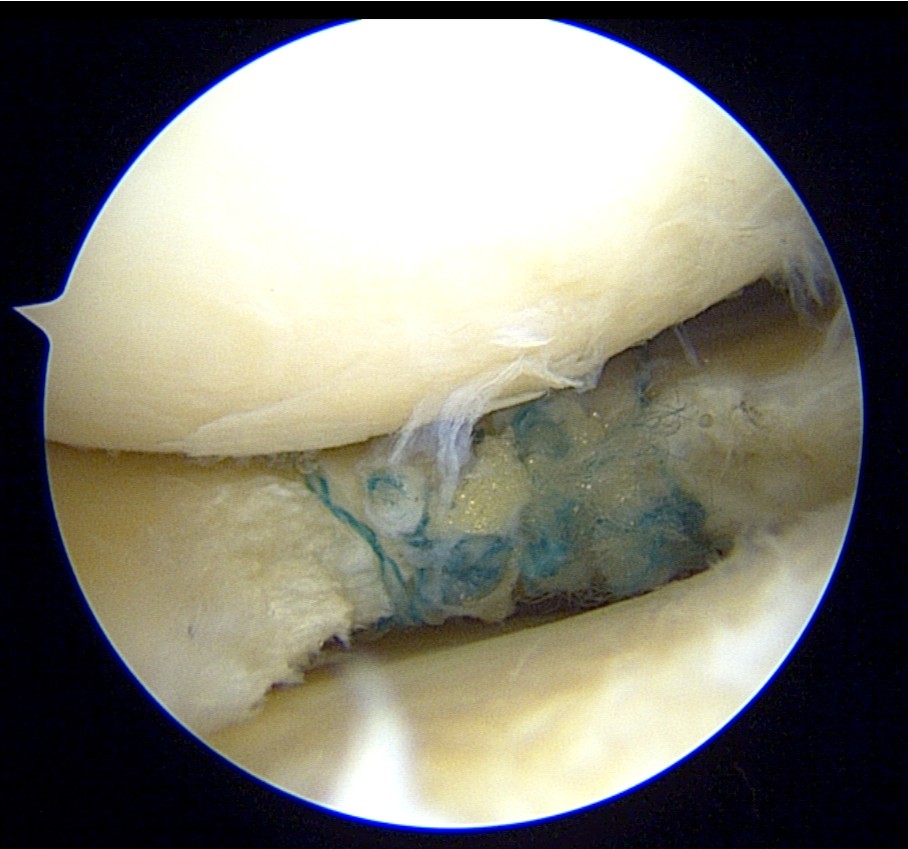

During arthroscopy, a horizontal cleavage tear in the lateral meniscus could be seen.

The cyst material was decompressed as much as possible through the tear.

The tear was then repaired using the Smith & Nephew’s NOVOSTITCH.